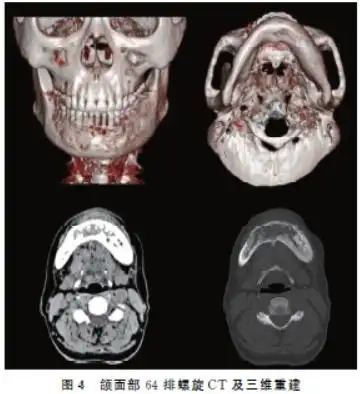

广西5龄童下颌骨长巨大肿瘤 手术成功康复出院

颌骨牙源性硬化性癌的影像学特征分析